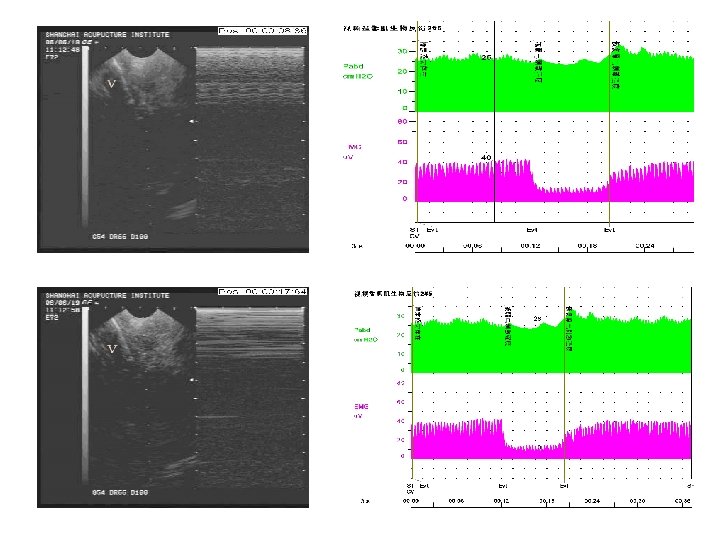

• Electrical pudendal nerve stimulation • After the needling sensation referred to the above regions was produced, a G 6805 -2 Multi-Purpose Health Device was connected with the inserted needles used as electrodes. The device was set to produce an electrical stimulation at a frequency of 2. 5 Hz (150 times/min) and an intensity as high as the patient could tolerate without discomfort. The electroacupuncture was set for 60 minutes each time. • 3. 电针阴部神经刺激疗法 • 针感达特定部位后接G 6805Ⅱ治疗仪。电针采 用连续波,频率约 2. 5 Hz (150次/分),强刺激 以患者不感到难受为度,每次持续 60分钟。

• Electrical pudendal nerve stimulation • Strong rhythmic and cephalad contraction of the pelvic floor muscles around the urethra must be kept during the electroacupuncture. • The treatment was given once every other day. The treatment course was based on the patient’s condition. • 电针期间需保持盆底肌以尿道为中心有节律地 向上(头部方向)强烈收缩的感觉。 • 治疗隔日 1次,治疗次数视病情而定。